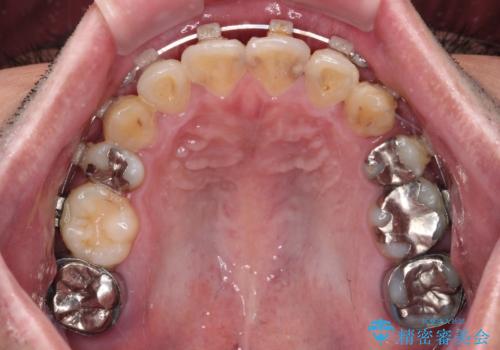

- 上下の八重歯やデコボコを気にして来院された患者様です。

上下ともに八重歯が顕著であったので、上下左右第一小臼歯4本を抜歯し、ワイヤー装置にて矯正治療を行うこととしました。

デコボコが強いことが原因で歯間部に汚れが溜まりやすい状態でしたが、矯正前にできる限り汚れが少なくなるようにブラッシングなどの指導を行い、口腔状態が改善された後にワイヤー装置を装着することとしました。